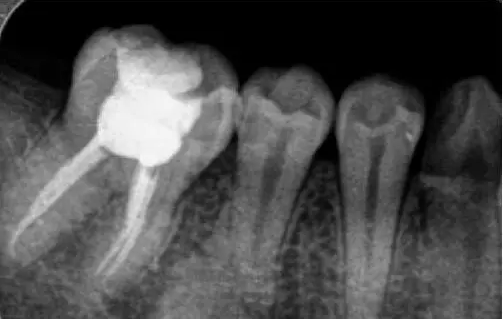

為什么根管治療需要拍多張片?

根管治療時,拍牙片是必要的,并且至少要保證3張牙片。

第一張:在治療前,幫助醫(yī)生了解牙根的基本情況,如根管預(yù)備是否到位等,并制定計劃。

第二張:在治療中,幫助醫(yī)生了解治療情況,如根管預(yù)備是否到位等,并指定下一步的計劃。

第三張:在治療結(jié)束后,幫助判定根管填充質(zhì)量,發(fā)現(xiàn)問題及時補救。